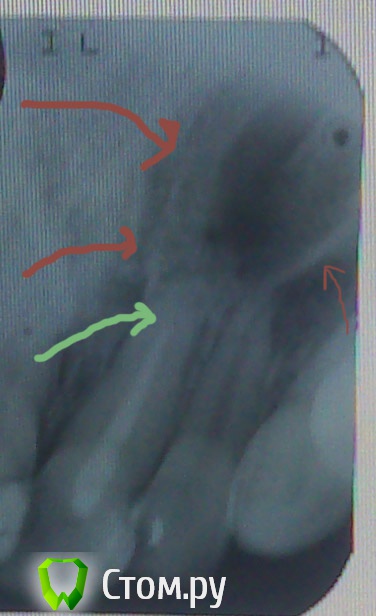

MaksimAleks Опубликовано 1 августа, 2014 Автор Поделиться Опубликовано 1 августа, 2014 Большое спасибо за внимание к моей проблеме. К сожалению, лучшее качество и ортопантомограмма в данный момент недоступны. Но исходя из нового прицельного снимка все таки киста 21? К нормальному стоматологу смогу попасть только через неделю. Насколько мне позволяет изучение данной тематики, это произошло из-за недопломбировки канала, но как только мне её произвели, уже было покраснение десны и через пару дней воспаление.Возможно ли такое быстрое развитие (киста была на зубе с живой пульпой)? А может всему виной его сосед 22, который уже как 9 лет депульпирован и на снимке имеет либо не запломбированный канал (как такое могло произойти в частной стоматологии) либо не контрастный материал? По виду он даже за эти десять лет почти и не изменился, в отличие от сильно потемневшего 21-го. В тоже время во время нагноения кисты чувствовалось давление на 22 сверху, быть может потому, что киста 21-го над ним?Через какой промежуток времени мне стоит обратится за имплантацией? Ссылка на комментарий

shishok Опубликовано 1 августа, 2014 Поделиться Опубликовано 1 августа, 2014 А может всему виной его сосед 22.Скорее всего.Лечение 21 без перелечивания канала в 22 бесполезно.Лечите оба зуба обязательно. Ссылка на комментарий